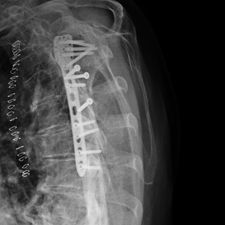

Ms. Q, age 74, initially presented on December 10, 2009, following a multiply comminuted, osteoporotic fracture of her left proximal Humerus. The decision was made to do an ORIF, which was carried out on December 14, 2009. She had a locking plate implanted following which she developed an infection of the wound. She was initially treated with antibiotics for this and she continued to get some oozing of the wound, which did not settle down despite continued use of the various antibiotics including Augmentin. Multiple wound swabs were done which failed to grow any organisms. The oozing persisted until about eight weeks following her operation when it finally settled down and the scar was noted to be tethered and was thought to be tethered onto bone.

She continued to have problems with intermittent cellulitis and pain in the arm and the decision was made to do an early removal of the metal work. This was carried out in mid March 2010 and at operation, which was done through the original incision and anterior extended deltopectoral approach, she was noted to have healed the fracture. She did well postop and was continuing to mobilize.